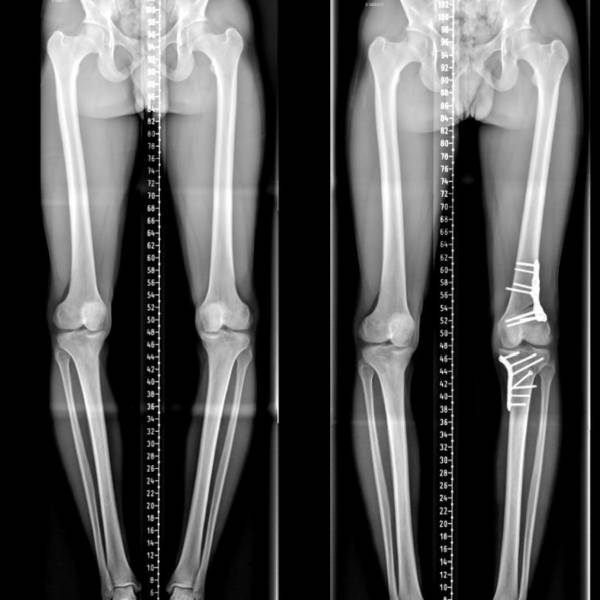

ostéotomie bifocale vue frontale

Révolutionner l'Ostéotomie du Genou : Le Leadership de l'Institut du Mouvement et de l'Appareil Locomoteur

Découvrez comment l'Institut du Mouvement et de l'Appareil Locomoteur redéfinit les standards en ostéotomie autour du genou, affirmant son rôle de leader mondial grâce à une performance clinique exceptionnelle, une contribution scientifique de premier plan, et une reconnaissance internationale incontestée